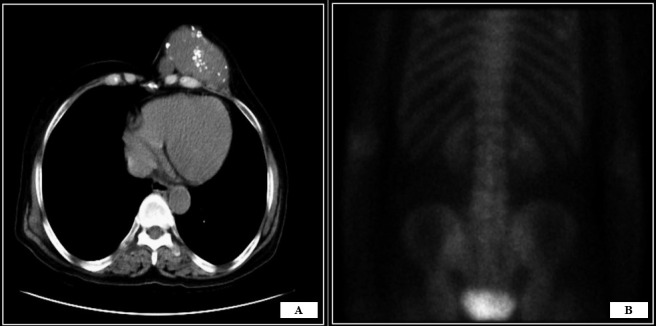

Breast sarcomas are a diverse group of malignant neoplasms originating from the mammary stroma. They are uncommon tumors, often occurring as a component of other tumors. Among malignant breast mesenchymal tumors, pure sarcomas lacking epithelial components are even rarer, comprising only 0.5% of breast tumors. The most common types include angiosarcomas, liposarcomas, and osteosarcomas. Pure, primary, and de novo chondrosarcomas are exceedingly rare within breast sarcomas, with very few cases reported. Distinguishing them from metaplastic carcinoma and phyllodes tumors with chondromatous areas entails extensive sampling to exclude proliferating ductal elements. Herein, we present a case of primary chondrosarcoma of the breast in a 72-year-old Indian woman. Initial core biopsy suggested a primary chondroid neoplasm or a heterologous component of a phyllodes tumor. The patient underwent modified radical mastectomy, and histological examination confirmed chondrosarcoma, grade 1, after thorough sampling.Clinical Relevance: This case emphasizes the necessity of incorporating rare sarcomatous breast tumors into the differential diagnosis for breast masses, especially those with chondroid differentiation. The report also reinforces the pivotal role of accurate histopathological evaluation in guiding appropriate surgical and adjunctive treatment, which can significantly impact prognosis in such rare malignancies.